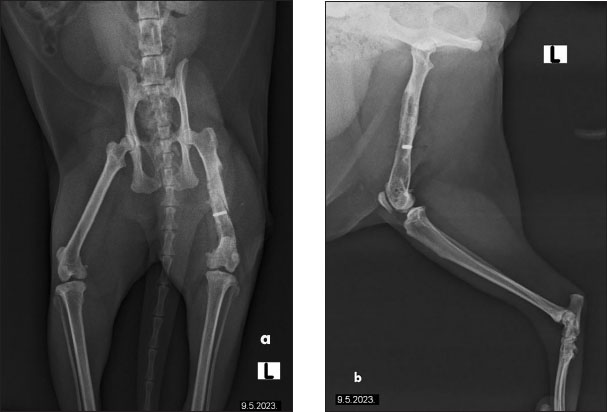

The cat had undergone orthopedic surgery 4 years ago, during which a plate was placed due to a femoral fracture (Fig. 2). Despite the surgery, the patient continued to show signs of discomfort, necessitating further diagnostics and therapy. During the examination at the radiology clinic, the cat showed signs of lameness and pain. The clinical examination revealed muscle atrophy of the left leg and pain on extension and flexion. Radiographic imaging of the pelvis and left femur revealed changes associated with the implant. Removal of the implant was recommended and subsequently performed. Figure 3 shows the radiographs of the cat’s left femur post-plate removal, showing 1 screw remaining in situ. Increased transparency in the medullary cavity indicates the need for LT to enhance healing and promote tissue regeneration.

Fig. 2. The radiographs of a cat’s left femur show (a) a ventrodorsal and (b) a mediolateral view following fracture repair using a 6-hole plate. The fracture is not visible, indicating satisfactory healing. Bone transparency is observed in the medullary cavity of the femur, further enhancing visualization of the internal bone structure. The plate is properly aligned, with no signs of complications.